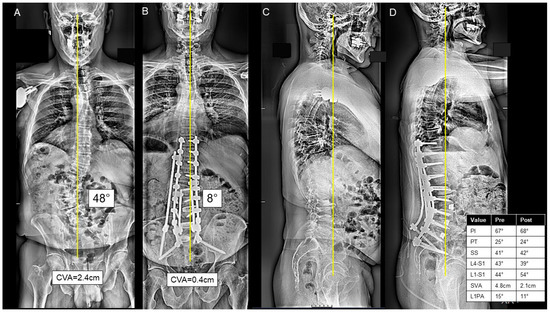

For patients in the AP group, the anterior approach consisted mostly of ALIF at L5/S1 (73.5%), L4/L5 (38.0%), L3/L4 (17.6%), L2/L3 (17.6%), and L1/L2 (2.9%). At L5/S1, the mean height of the implant was 10.9 ± 3.0 mm, and mean lordosis was −23.2 ± 32.5°. At L4/5, the mean height of the implant was 10.2 ± 3.0 mm, and mean lordosis was −10.7 ± 16.2°. Half of the AP cases were staged 18 (52.9%), separated by a mean of 2.1 (range 1–5) days. A three-column osteotomy was performed in 10 (29.4%) cases. A thoracolumbar UIV to sacrum/pelvis fusion was performed in 16 (47.0%) cases, and an upper/middle thoracic to sacrum/pelvis fusion was performed in 15 (44.1%) cases. A representative combined AP case is presented in Figure 3A–D.

Figure 3.

(A–D) A case presentation of a 67-year-old male presenting with L3-L4 left-sided radiculopathy and sagittal malalignment due to lumbar kyphosis causing severe mechanical back pain on the postero-anterior (PA) (A) and lateral X-rays (C). The patient underwent a stage 1 anterior lumbar interbody fusion at L4-5 and L5-S1. Two days later, the patient underwent a posterior approach consisting of T10-ilium instrumentation, posterior column osteotomies from T12-L5, inferior facetectomies from T10-S1, and L2/L3 and L3/L4 transforaminal lumbar interbody fusion, as seen on the postoperative PA (B) and lateral X-rays (D). The patient was discharged to IPR at postoperative day 9.